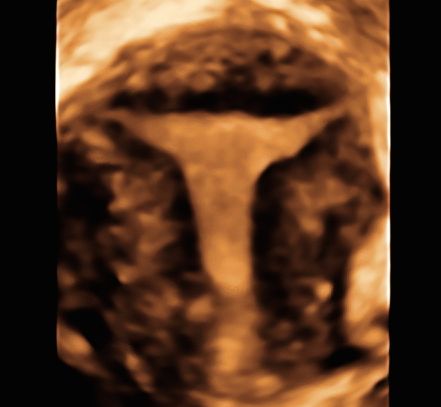

Sono esperta in ecografia 3D (tridimensionale) di cui sono stata docente a livello nazionale ed internazionale per oltre 20 aa, rivestendo incarichi nazionali nell'ambito della Società di Ecografia in Ostetricia e Ginecologia (SIEOG).

• malformazioni uterine

• setto uterino

• utero bicorne

ecografia 3D Da 260 €